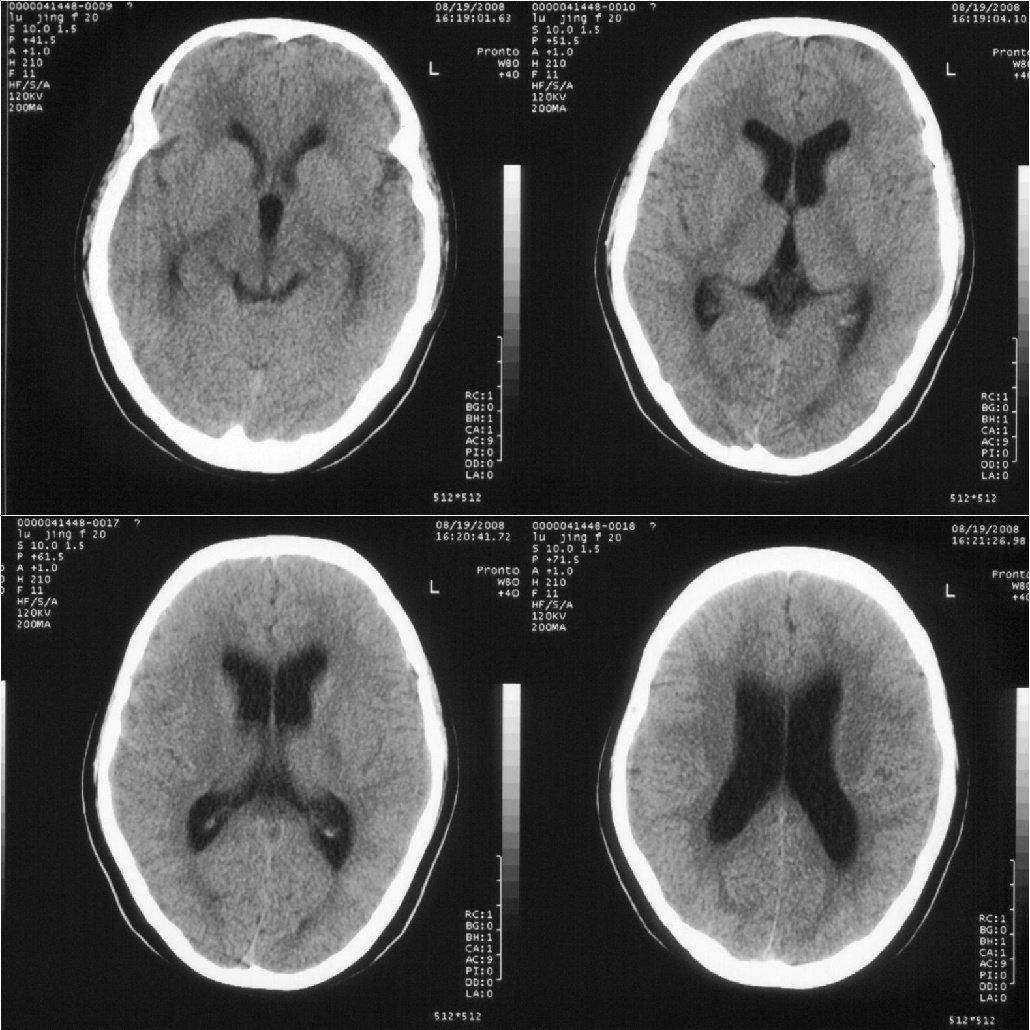

女,20岁。3天前突然恶心、呕吐,当时意识尚清楚。随后睡了一觉,醒后意识丧失,一直持续约5个小时左右才恢复意识。现在意识清楚,但一直干呕。

轻度脑积水,建议mr检查.

侧脑室系统轻增宽,支持轻度脑积水,建议mri

双侧脑室及三脑室轻度增大,第四脑不大。考虑幂上脑积水,可能中脑导水管不完全阻塞可能。

追踪回访:脑压测定200,现在已经正常上学

脑室稍扩大,支持轻度脑积水诊断.

十楼的朋友说鞍上池有低密度占位,我认为那是扩大的三v.